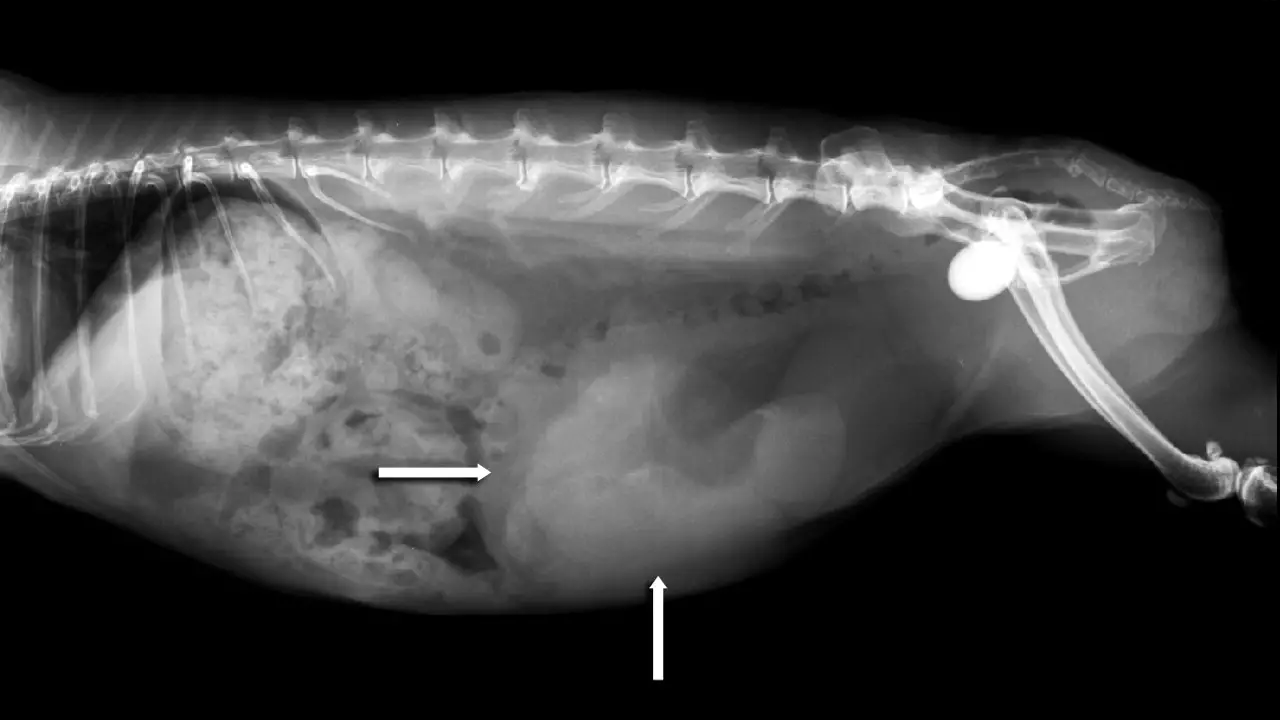

Xray of the Abdomen of a Rabbit with Stones in the Bladder and Urethra Pregnant Rabbit Xray This can be done later in the pregnancy to get a. In the present study pregnancy. How early can i scan a rabbit? Confirming the pregnancy with a veterinarian is a top priority to ensure your pregnant rabbit’s proper care and support throughout her pregnancy. Rabbit pregnancy tests work by various methods such as ultrasound imaging to visualize fetal structures,. Pregnant Rabbit Xray.